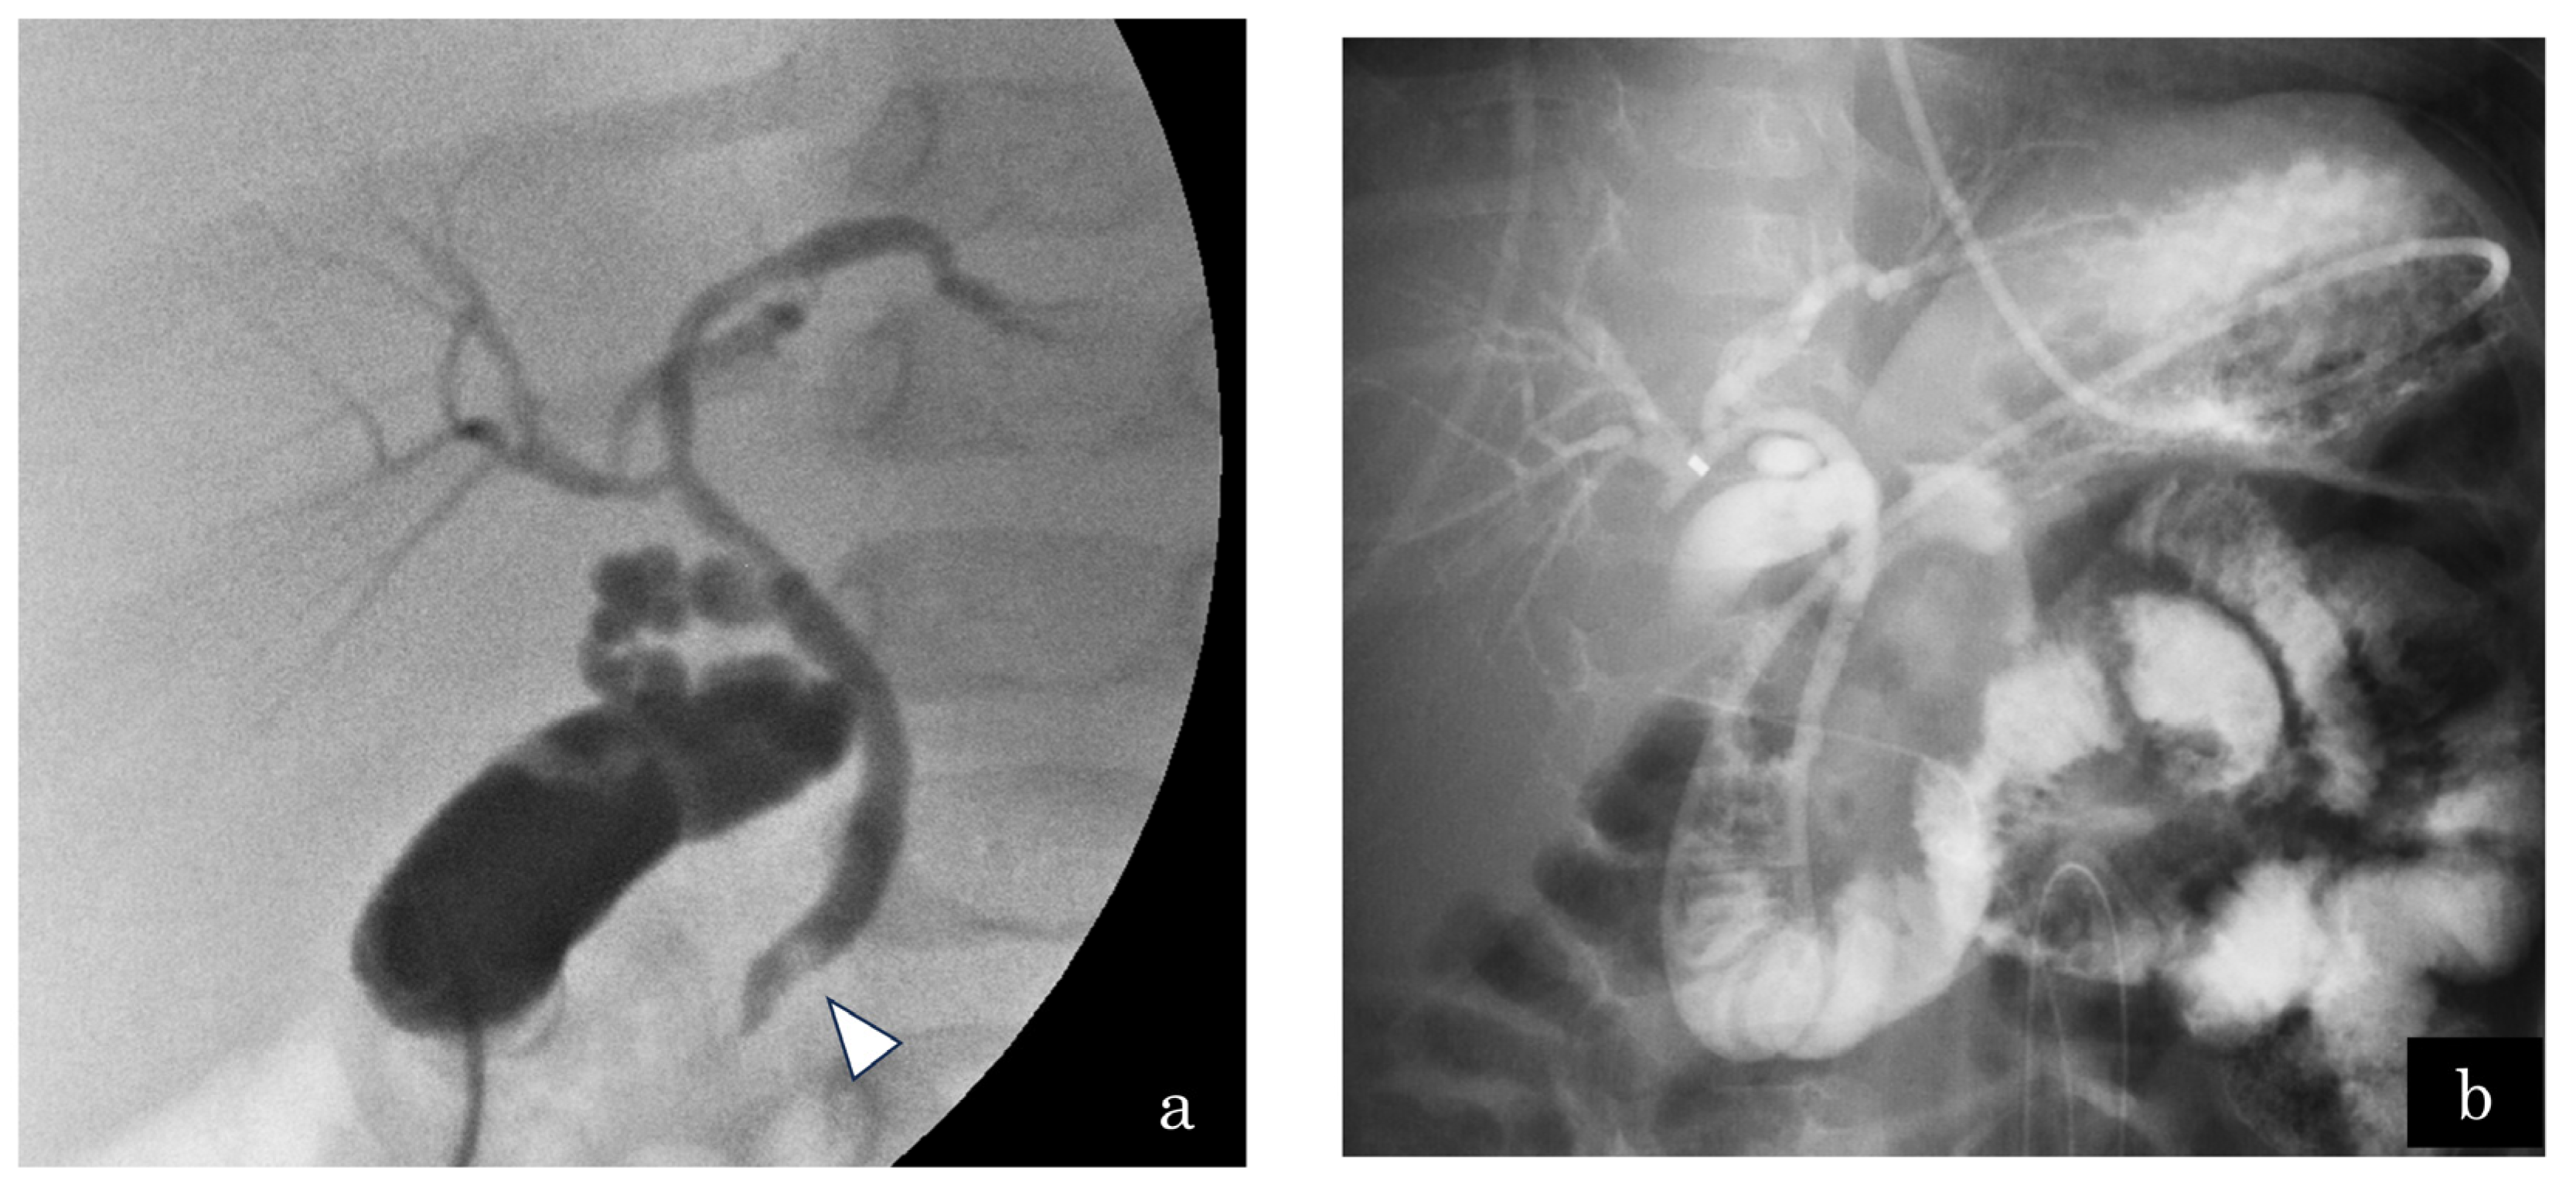

A 5-month-old girl presented with vomiting. US demonstrated multiple gallbladder stones and gallbladder wall thickening. The patient further presented with septic shock and then underwent emergency gallbladder drainage. Intraoperatively, one CBD stone was affecting the distal CBD (Figure 4a) and an ENBD tube was inserted (Figure 4b). Endoscopic papillary balloon dilatation was performed to remove the CBD stone after treating septic shock. The length of the CC was 2.4 mm; however, the SO segment could not be measured because of the patient’s small size. Lipase in the serum and bile juice obtained during gallbladder drainage and ENBD were assessed (Figure 5). The lipase level in bile juice obtained during gallbladder drainage was sometimes elevated even after ENBD removal (up to 3696 IU/L). This indicated that PBR occurred intermittently in this case, which induced gallbladder and CBD stones in the 5-month-old infant. She underwent bilio–jejunal anastomosis, with an uneventful clinical course postoperatively.

Figure 4.

Case 7: A 5-month-old girl presented with gallbladder stones on ultrasonography. The patient developed septic shock due to cholangitis. (a) Emergency gallbladder drainage was performed, and a bile stone located in the distal common bile duct (white arrowhead) was observed. The pancreatic duct was not visualized by cholangiography. (b) A 4-Fr endoscopic nasobiliary drainage tube was inserted.